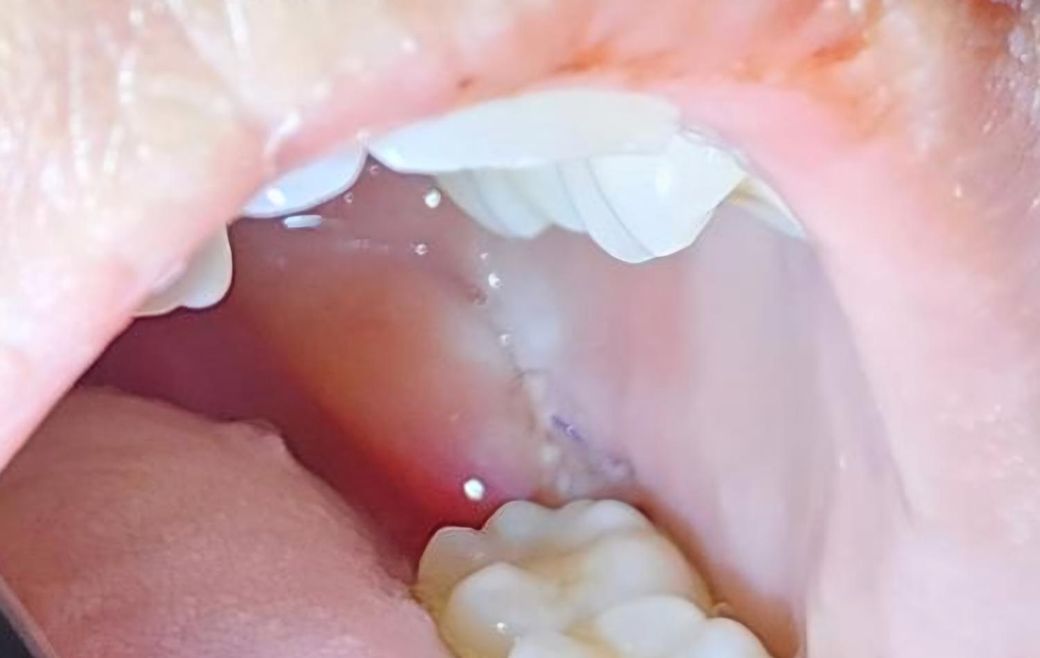

사랑니 발치 후 잘 아물고 있는건가요?

사랑니 발치 후 3일차인데 자다가 피떡이 사라지고

하얗게 올라와있어요ㅠㅠ

음식물 또는 염증일까요?

아니면 잘 아무는 중인가요

밥알이 낀 거 같기도 하네요..

사진 상 큰 문제는 보이지 않습니다. 음식물 끼임 등에 대해서 관리만 조금 더 잘해주시면 됩니다.

사진으로 보기에는 큰 문제없이 치유중인 것으로 보입니다. 걱정하지는 않으셔도 되겠고 혹여 통증이 점차 심해진다거나 볼이나 턱쪽이 부어오르는 경우에는 치과에 내원하시면 되겠습니다.

사진상으로 보면 크게 문제 없이 잇몸이 잘 아물고 있으니 음식물이 남지 않도록 잘 헹궈주시는게 좋습니다.

염증 육아조직으로 발치후 치유과정에서 생기게 됩니다 해당부위 음식물끼어있지 않게 가볍게 물로 헹궈주세요

사진으로만 봤을 경우에는 크게 문제가 없이 아물고 있는것으로 보입니다.